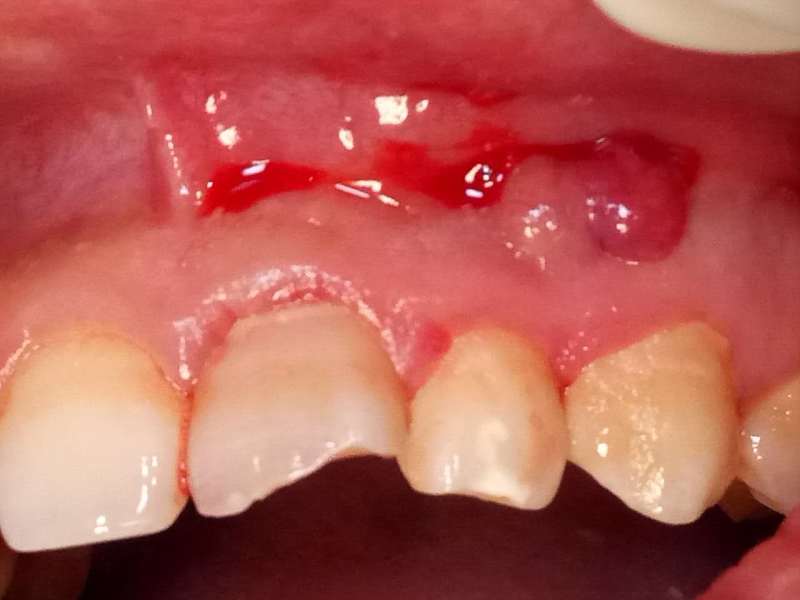

死髓牙2度,沒保留價(jià)值了,外傷造成的外吸收,即使到充也容易出問題。和患者溝通,要求做種植,用了兩個(gè)骨膠原,側(cè)切、尖牙沒事,側(cè)切做了一次根充